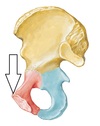

Ischial spine